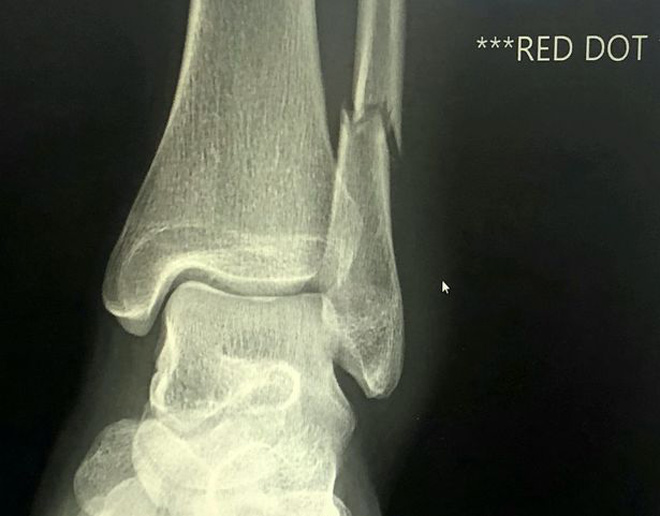

Dù vậy, cô đã kết thúc chặng đua marathon với thời gian 6 giờ 14 phút. Sau khi hoàn thành 42 km và nhận kỷ niệm chương, O’Keeffe đã ăn mừng với gia đình, bạn bè. Sáng hôm sau, cô đến phòng cấp cứu và được chụp X-quang. Kết quả cho thấy cô bị gãy xương mác ở gần mắt cá chân.

Phim chụp X-quang cho thấy rõ mắt cá chân bị gãy của Siobhan O'Keeffe

“Bác sĩ phẫu thuật chỉnh hình đã phải thốt lên rằng ông không biết làm sao mà tôi có thể chạy với tình trạng như vậy. Ông ấy nói đó là một chấn thương và không thể tin là có thể như thế được”, O’Keeffe kể lại.